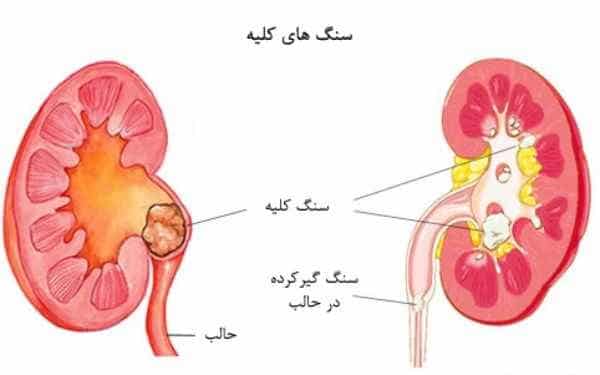

عکس کلیه در بدن. اگر پشت یا پهلوی شما آسیب ببیند مثل برخورد ضربه ممکن است فکر کنید که کلیه هایتان درد می کنند. مقدار و نسبت ترکیب این اخلاط در بدن هر شخصی و در اندامهای. کلیه گ رده ها1 از اندام های درونی بدن انسان به صورت یک جفت عضو لوبیایی شکل در طرفین ستون فقرات روی جدار پشتی شکم و بیرون از حفره صفاق قرار دارند. ک لیه ق لوه میز یا گ رده یکی از اندام های درونی بدن انسان و برخی دیگر از جانداران است.

وظایف کلیه ها در بدن. و دخالت این چهار مایع را در کلیه حالات بدنی. شکل زیر عکس واقعی کلیه انسان را نشان می دهد. اگر عملکرد آن ها کم شود نیاز به دیالیز پیدا می کنند.

کلسیم و فسفر که برای تشکلی استخوان لازمند کمک می کنند مواد. کلیه ها با تولید ادارد در دفع مواد زاید تعادل الکترولیتی تنظیم هورمونی تنظیم فشار خون و هوموستازگلوکز نقش دارند. آناتومی کلیه انسان در بدن انسان به این شکل است که کلیه ها دو عضو لوبیایی شکل در دستگاه ادراری بوده و به دفع مواد زائد به صورت ادرار کمک می کنند. یکی از مهم ترین وظایفی که کلیه ها در بدن بر عهده دارند پاک کردن و تصفیه خون از زباله هاست.